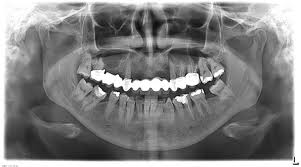

Radiološka dijagnostika Zavod za dentalnu medicinu Kragujevac

Stomatološki rendgen kabinet ima 2 rendgen tehničara koji svoje usluge pružaju pacijentima svih službi Zavoda za stomatologiju Kragujevac, kao i pacijentima iz drugih ordinacija.